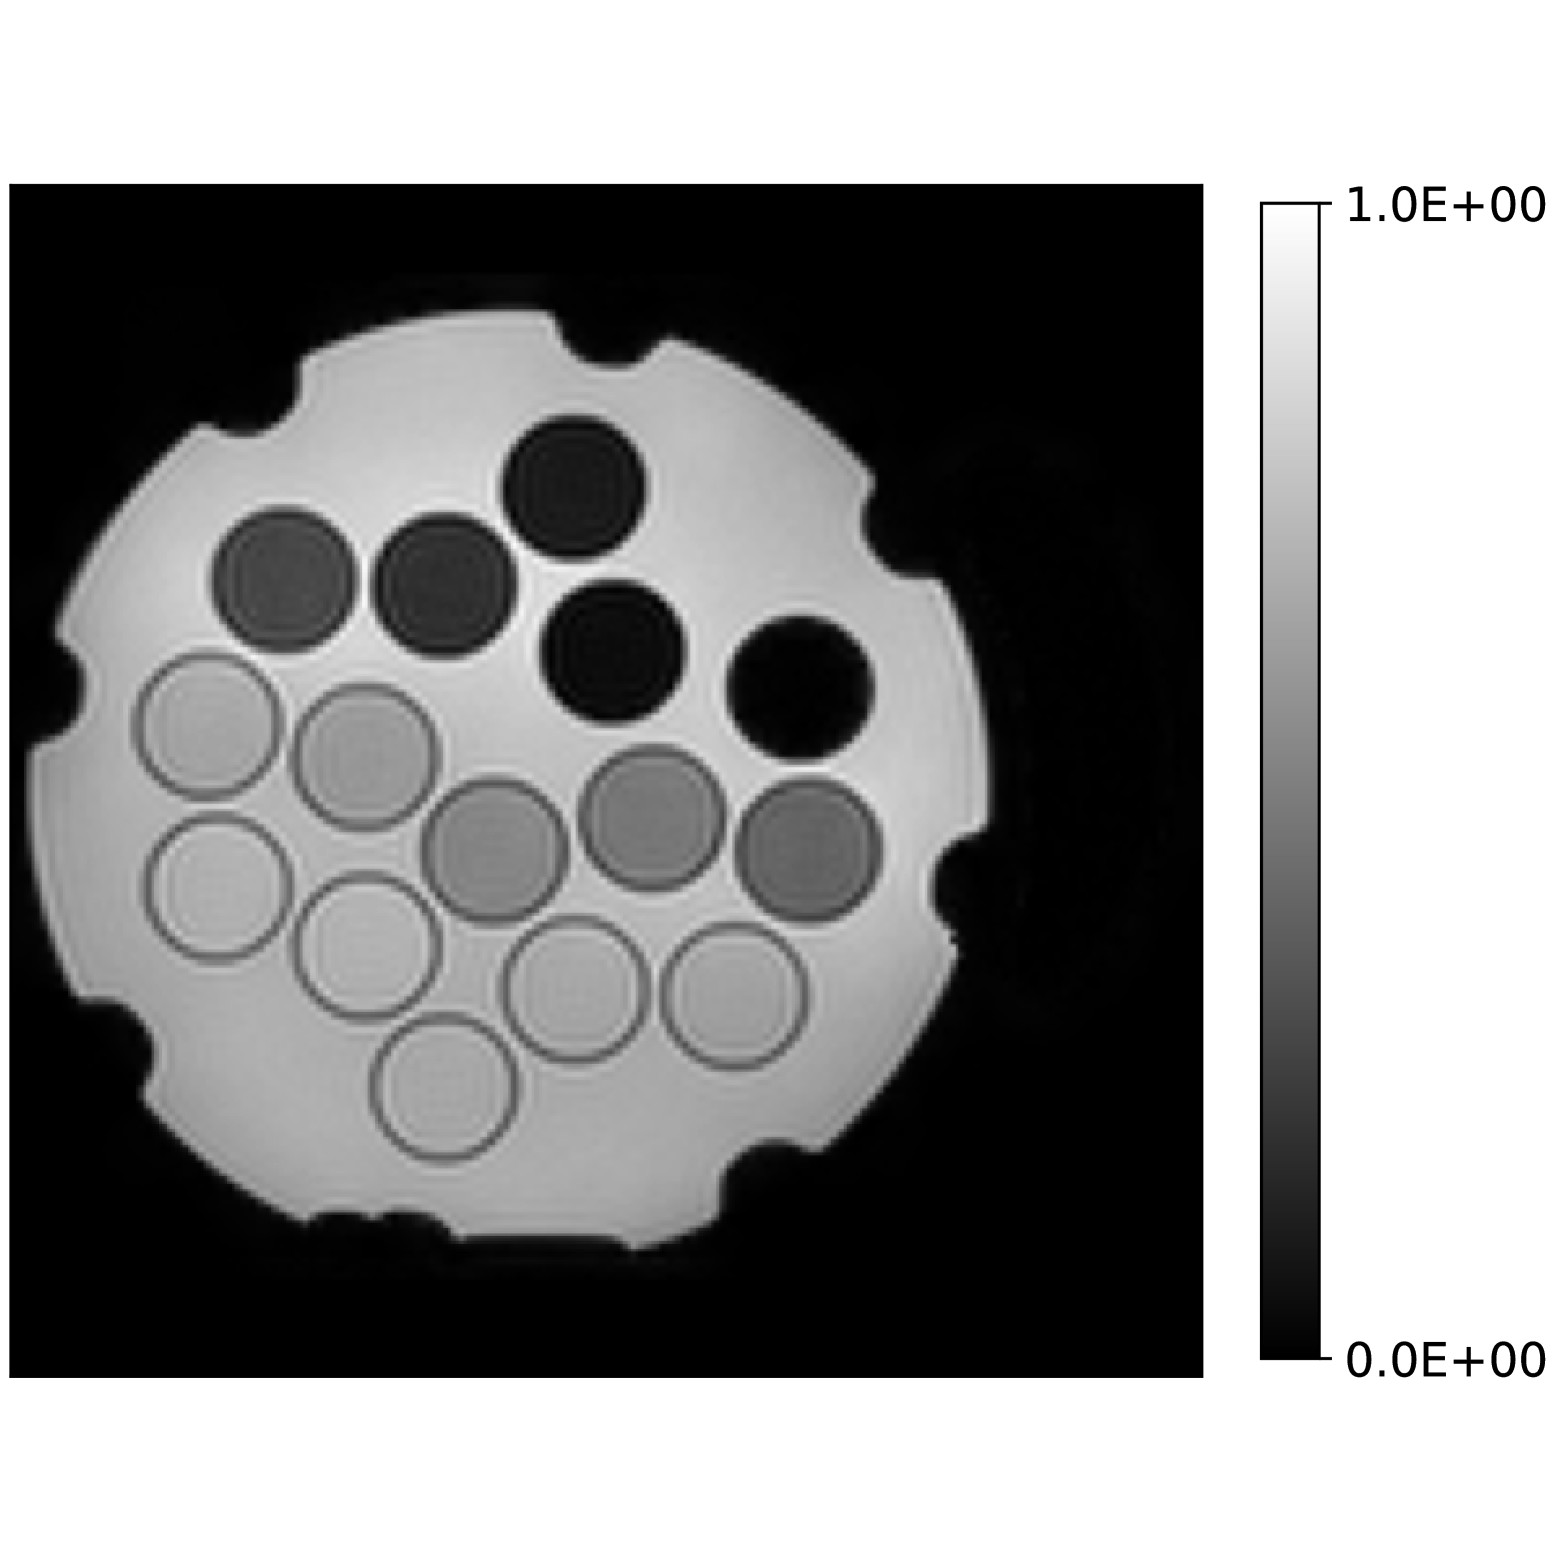

Our theoretical results show that generic concentrations and maps can be recovered exactly even when the fieldmap is not identifiable. To illustrate the impact of this fact, we perform a recovery experiment on a water (Fig. 2(a)), fat (Fig. 2(b)) and silicone (Fig. 2(c)) in silico phantom. The concentrations are all real. The values for the fieldmap and used to generate the signal are shown in Figs. 2(d) and 2(e). The echo times have the form where ms and ms with .

In Figs. 2(f), 2(g) and 2(h) show the recovered concentrations of water, fat and silicone, and Fig. 2(j) shows the recovered . These recovered quantities are all qualitatively similar to their true values. In contrast, Fig. 2(i) shows the recovered fieldmap, which differs from its true value. By comparing the errors in the recovered concentrations, we see that they are within a reasonable accuracy except in regions with a large magnitude for the fieldmap gradient, indicating a bound that is too small (Figs. 2(k), 2(l) and 2(m)). A similar behavior is seen in the recovered (Fig. 2(o)). The error for the recovered fieldmap tends to be larger outside the area of the phantom (Fig. 2(n)).